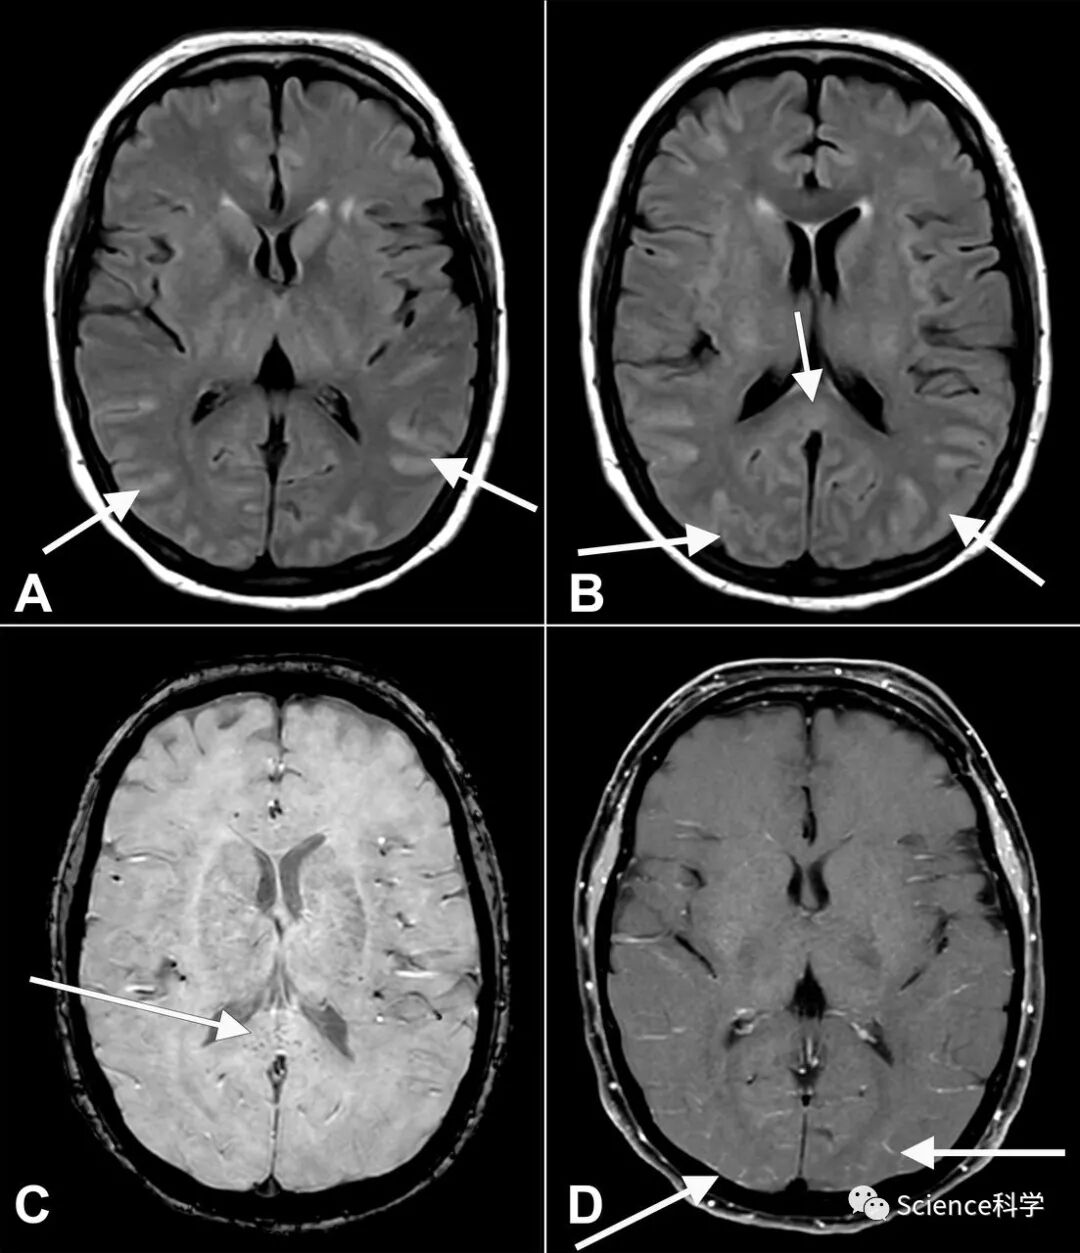

在COVID-19大流行病发生一年多后,研究人员揭示了病人在住院期间和住院后可能面临的许多破坏性后果。一项对大流行初期因COVID住院的近150名病人的新研究发现,73%的病人患有神志失常,这是一种严重的精神状态紊乱,病人会感到困惑、烦躁、无法清晰思考。

疾病本身会导致大脑的氧气减少以及血栓和中风的发生从而导致认知障碍。此外,炎症标志物在神志失常患者中大大增加。混乱和烦躁可能是大脑炎症的结果。